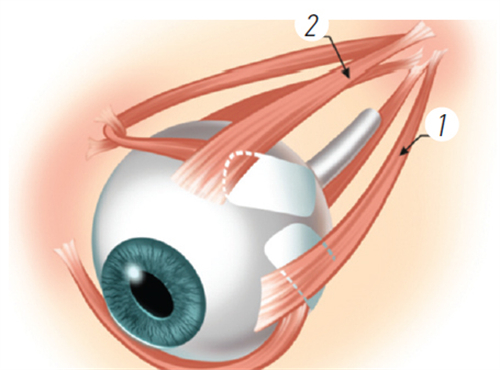

孙医生在玻璃体视网膜手术方面具有独特技术优势,采用国内外靠前的小创口玻璃体切割技术治疗复杂性视网膜脱离,手术成功几率达90%以上。

精细操作:在显微镜下完成视网膜前膜剥离、激光光凝等步骤